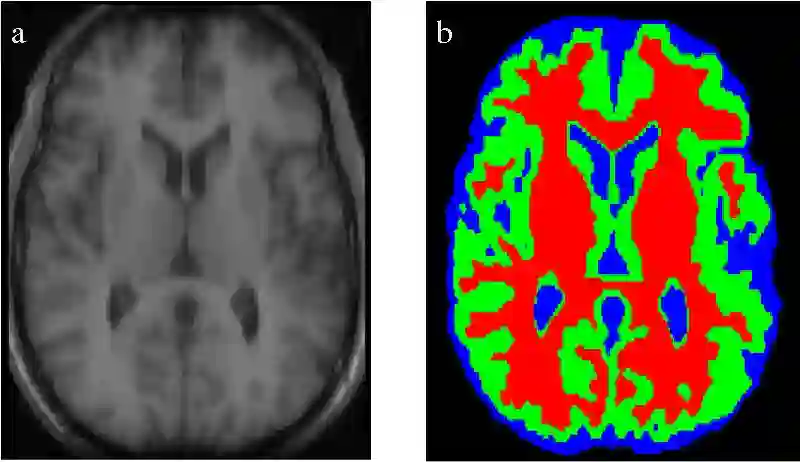

医学影像分割

语义分割技术也被用于在医学扫描影像中识别显著性元素。该方法对识别图像中的异常(如肿瘤)十分有效。提升算法的准确率并解决低召回率的问题对于这种应用十分重要。

医学扫描影像的分割

我们还可以将一些不那么关键的操作自动化处理,比如根据语义分割后的 3D 扫描影像估计器官的体积。